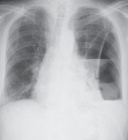

A Comissão de Seguridade Social e Família discute hoje, às 14h30, aspectos relacionados à linfangioleiomiomatose (LAM). A LAM é uma doença rara que com o tempo causa a obstrução dos pulmões.

O debate foi sugerido pelo deputado Diego Garcia (PHS-PR) e Alan Rick (PRB-AC). Os parlamentares destacam que a LAM se caracteriza pela proliferação desordenada de células musculares lisas e não tem etiologia muito bem conhecida.